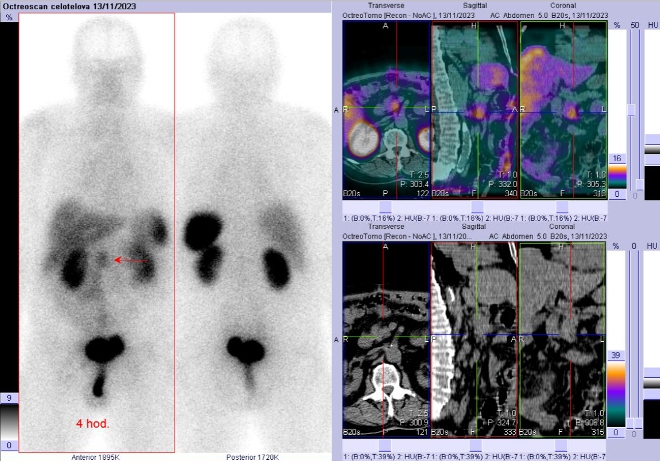

Scintigrafie Octreoscanem:

I. v. jsme aplikovali 190 MBq analogu somatostatinu značeného 111In

(přípravek OctreoScan firmy Curium Netherlands B. V.) a provedli pomocí hybridní tomografické scintilační kamery Symbia T2 firmy Siemens opatřené kolimátory pro střední energie planární celotělovou scintigrafii a cílenou tomografickou scintigrafii (SPECT) břicha a pánve kombinovanou s CT za 4 a 24 hod.

(obr. 1-2).

/ Obr. č. 1: Celotělová scintigrafie a SPECT/CT za 4 hod. po aplikaci OctreoScanu.

Popis: Za 4 a 24 hod. je patologické ložisko zvýšené depozice radioindikátoru v uzlině u hlavy pankreatu. Jinak pozorujeme fyziologickou depozici radioindikátoru ve slezině, játrech, ledvinách, močovém měchýři, střevech.

Závěr: patologické ložisko se zvýšenou hustotou somatostatinových receptorů v uzlině u hlavy pankreatu. Nález svědčí pro uzlinovou metastázu neuroendokrinního nádoru.